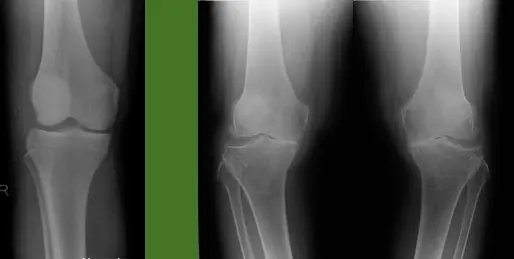

| Look | Compare both limbs, Skin, Muscle bulk, bony landmarks, hair distribution | Assess symmetry, signs of trauma, inflammation, muscle atrophy, structural changes | Visual examples - Skin, Muscle, Bone, Joint: ![]() ![]() ![]() ![]() ![]() ![]() | Swelling, scars, discoloration, hair changes, muscle wasting, bony protrusions, angulation, redness |

| Special Tests | Collateral Ligaments: Varus and Valgus stress at 30 degree | Assess integrity of Medial (Valgus) and Lateral (Varus) Collateral Ligaments | Collateral Ligament Testing: Collateral Ligament Testing Views: Alternative Collateral Ligament Technique: ![]() | Increased laxity or pain during stress, indicating ligamentous injury |